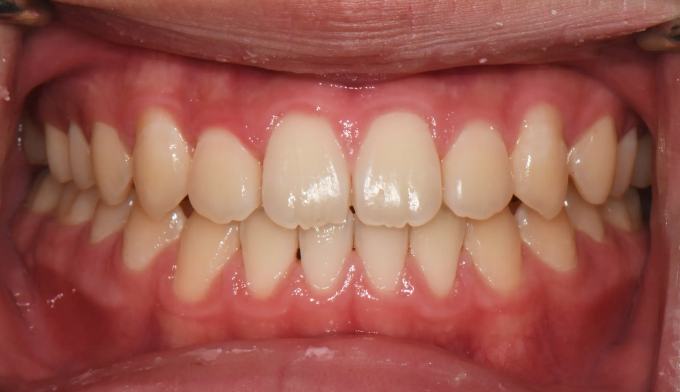

주걱턱 경향을 갖는 청소년들은 개방교합과 덧니를 동시에 갖는 경우가 많습니다. 아래턱의 과도한 성장은 혀의 위치를 아래로 처지게 만들고, 이는 위턱의 폭을 줄어들게 만들어 덧니가 생기기 쉽게 만듭니다. 그리고 과도한 아래턱의 성장은 앞니의 교합을 벌어지게 만들어 개방교합 또한 나타나게 됩니다.

그 정도에 따라 발치가 필요한 경우도 있지만, 성장기의 청소년의 경우에는 최대한 발치 없이 자연스러운 치열과 입매를 만드려고 합니다.

좁아진 위턱 악궁을 확장시켜서 치아를 배열시키고, 과도하게 앞으로 나온 앞니를 미니스크류를 이용하여 후방이동 시킵니다.

총 치료기간은 24개월 소요되었습니다.